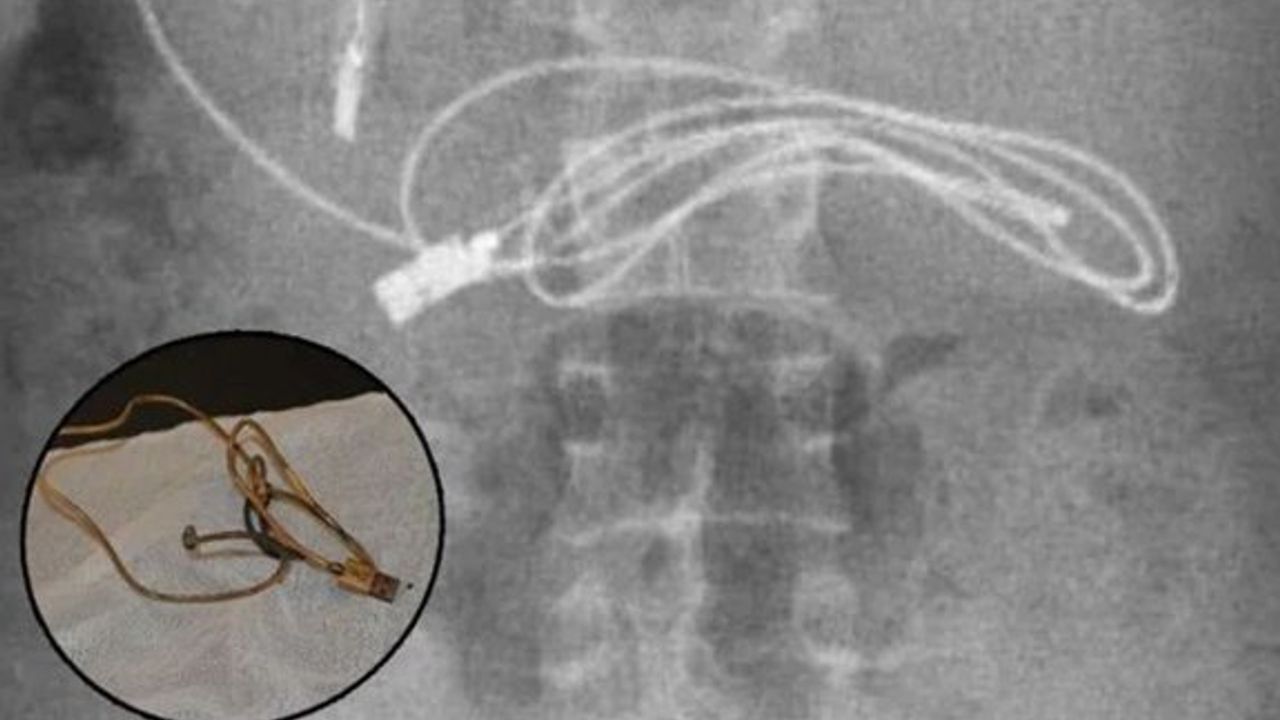

Kusma ve bulantı şikayetiyle ailesi tarafından hastaneye götürülen erkek çocuğunun çekilen röntgeninde, midesinde şarj kablosu ve toka olduğu görüldü.

Üniversitenin Çocuk Gastroenteroloji Hepatoloji ve Beslenme Bilim Dalı Başkanı Prof. Dr. Yaşar Doğan ve ekibi tarafından yapılan endoskopik işlemle çocuğun midesindeki kablo ve toka başarıyla çıkarıldı.

Ameliyatı gerçekleştiren Prof. Dr. Yaşar Doğan, kablonun bir ucunun ince bağırsağa geçmesi nedeniyle zorlandıklarını ifade ederek, “Hastanın kusma ve karın ağrısı şikayetleri olması üzerine sağlık kuruluşuna başvurulmuş. Orada yapılan incelemelerde hastanın midesinde kablo tespit edilmesi üzerine bize danışıldı'' dedi.